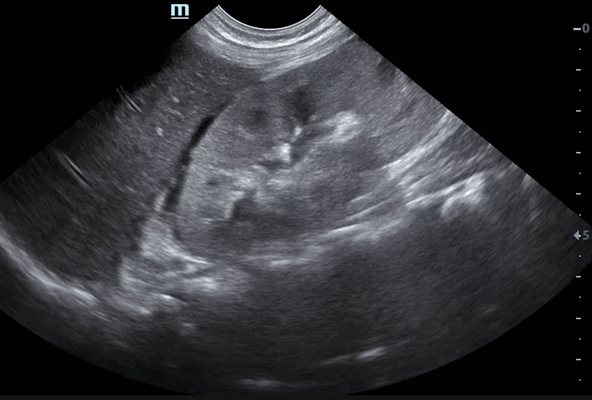

- УЗИ почек. При почечной эхографии онкоцитома визуализируется как гипоэхогенное образование, вызывающее деформацию органа. Размеры узла чаще не превышают 10 см. УЗИ в допплеровском режиме обнаруживает гиперваскуляризацию онкоцитомы, что может привести к ошибочной диагностике рака почки.

Как выглядят опухоли почек на УЗИ

- Онкоцитома — доброкачественная опухоль, встречающаяся у мужчин пожилого возраста. Из-за невысокой плотности на УЗИ выглядит темной. Опухоль часто перерождается в рак, поэтому от нее рекомендуют избавляться.